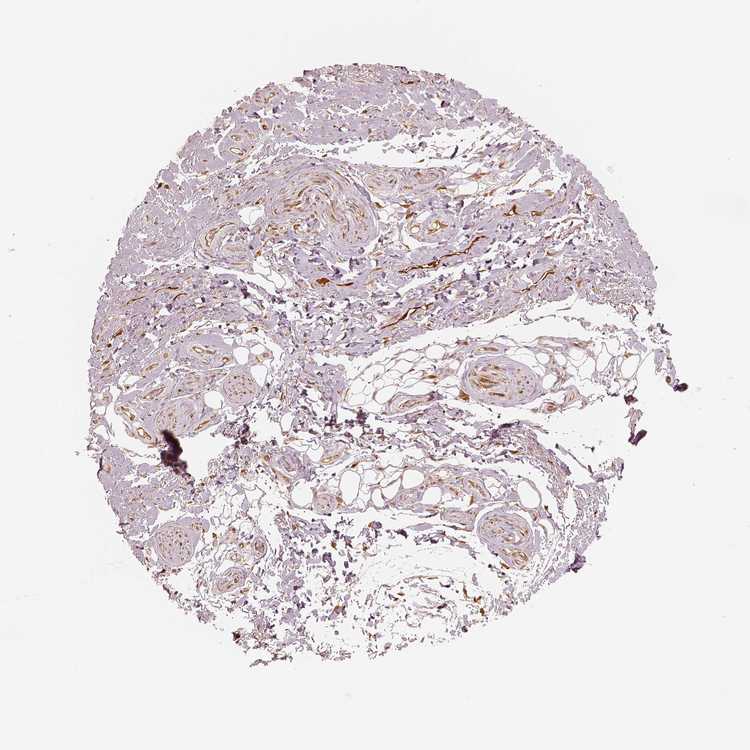

SOFT TISSUE 1 - Antibody stainingi

Antibody staining in the annotated cell types in the current human tissue is reported as not detected, low, medium, or high, based on conventional immunohistochemistry profiling in selected tissues. This score is based on the combination of the staining intensity and fraction of stained cells.

Each image is clickable and will lead to virtual microscopy that enables deeper exploration of all samples and also displays staining intensity scores, fraction scores and subcellular localization as well as patient and tissue information for each sample.

Antibody HPA005723Antibody HPA050654Antibody CAB000121Antibody CAB035991

Chondrocytes MediumLowMediumMedium

Fibroblasts MediumMediumNot detectedMedium